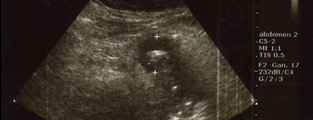

Sensibilidad y especificidad de los signos ultrasonográficos de apendicitis aguda

Sensibilidad y Especificidad de los signos ultrasonográficos de Apendicitis Aguda […]